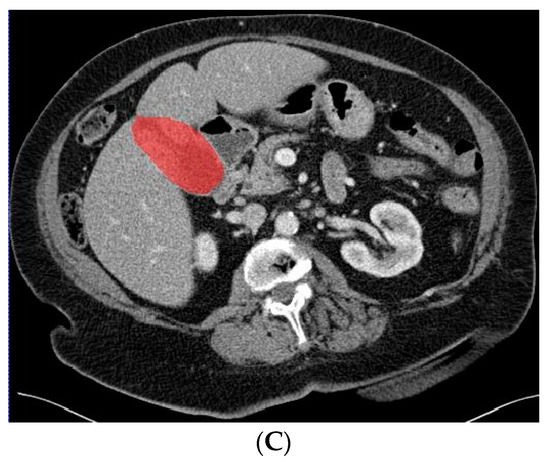

Figure 2.

Axial CT slice (A) with an example of gallbladder cancer (histopathologically proven adenocarcinoma, encircled in (B)) and subsequent segmented gallbladder (C).